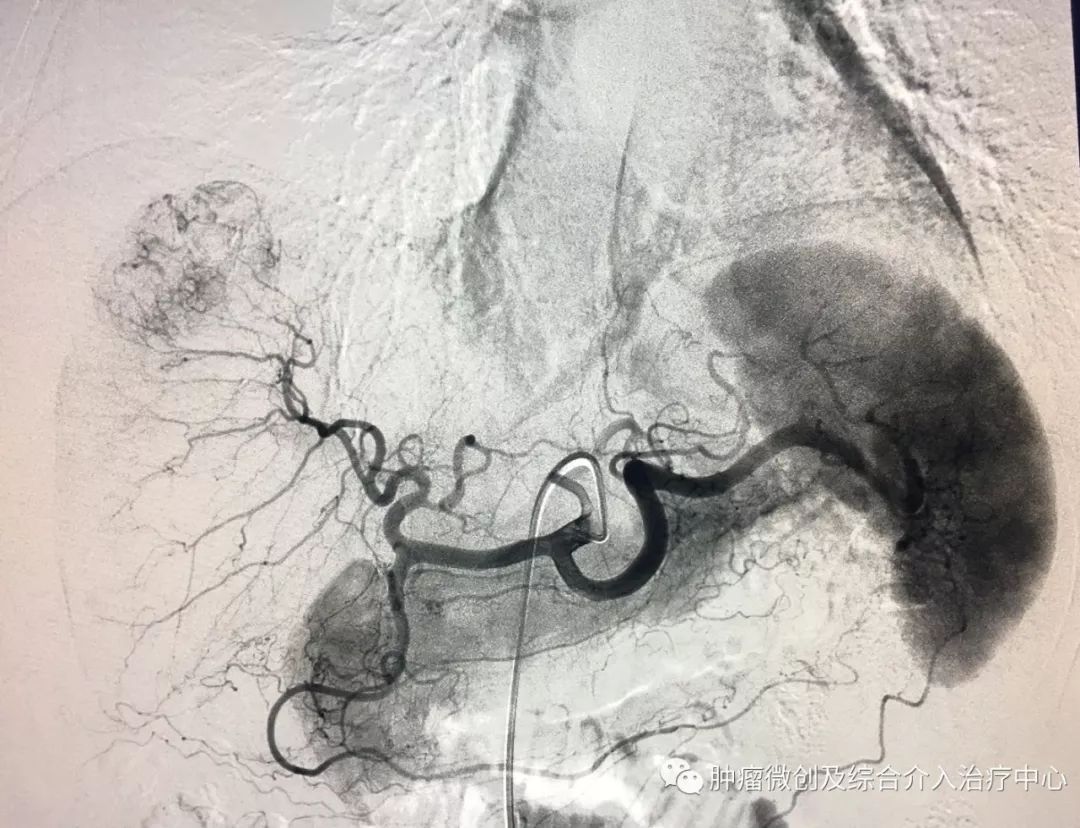

(术前DSA造影提示子宫动脉增粗、迂曲、紊乱,临床表现间歇性出血)

(介入栓塞术后病变动脉栓塞好,血管走向规整,出血停止)项目简介:子宫动脉出血栓塞常应用于妇产科疾病,如产后出血,胎盘植入或子宫恶性病变等,尤其适用于产后大出血,危及产妇生命的病例,介入栓塞有着微创、依从性好、止血疗效确切的优点。06支气管扩张咯血介入治疗